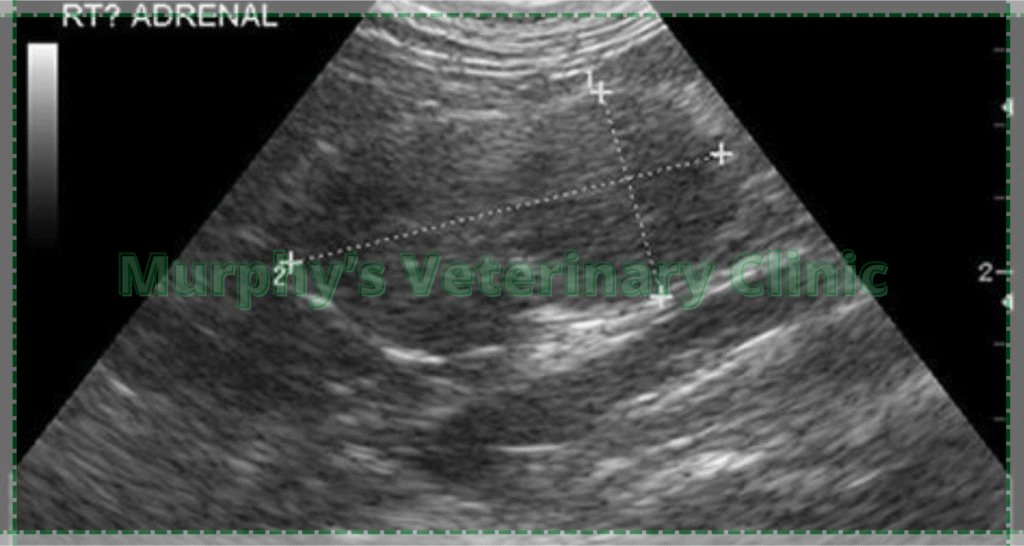

Diagnosing this condition requires advanced veterinary testing. It includes a combination of physical examination, blood/urine tests, and imaging. Common tests include ACTH stimulation or low-dose dexamethasone suppression. These help evaluate the functionality of the pituitary and adrenal glands. Ultrasound or CT scans are used to locate possible tumors. An accurate diagnosis is the foundation for successful treatment.

| Abdominal Ultrasound | Checks gland size and tissue condition |